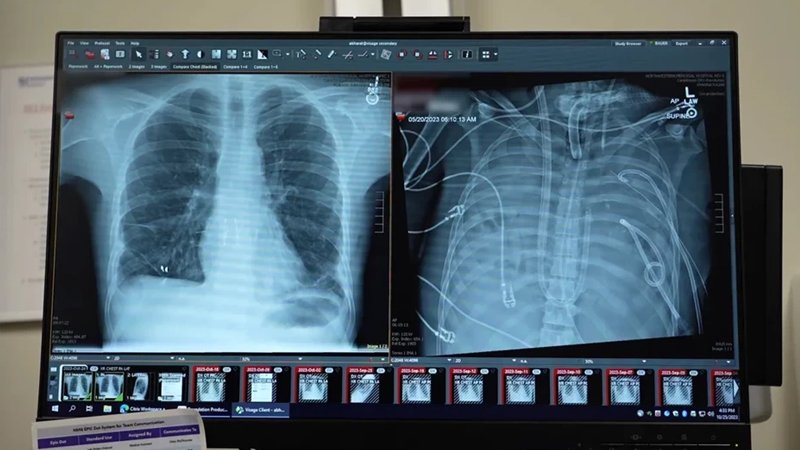

Əlavə müayinələr qərarı asanlaşdıra bilər. Boyun Doppler ultrasəsi (karotid arteriya ultrasəsi) və koronar KT angioqrafiyası (virtual angioqrafiya) xüsusilə orta və yüksək ürək riski olan şəxslərdə aparılır. Bu testlər zamanı lövhə aşkar edilərsə, qan durulaşdırıcıları tövsiyə olunur.